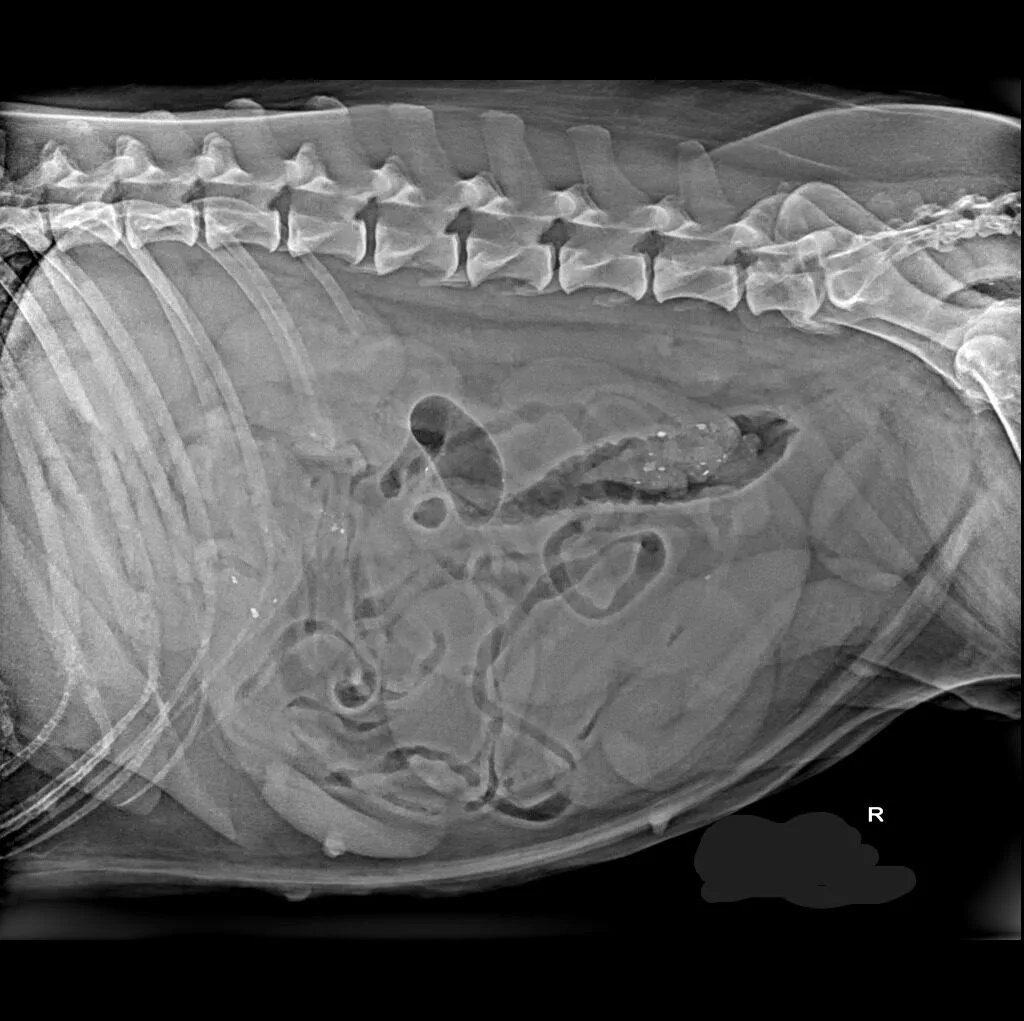

At Grand Ave. Pet Hospital, we utilize digital radiography to diagnose and monitor a wide range of medical conditions in pets. Digital X-rays provide clearer images, faster results, and safer radiation levels, ensuring the best possible care for your furry companion.

Digital radiography offers superior imaging quality and precision compared to traditional X-ray techniques. It allows us to detect hidden health issues early, leading to faster and more effective treatments.

🔹 Abdominal & Gastrointestinal Issues – Detecting obstructions, tumors, or organ abnormalities